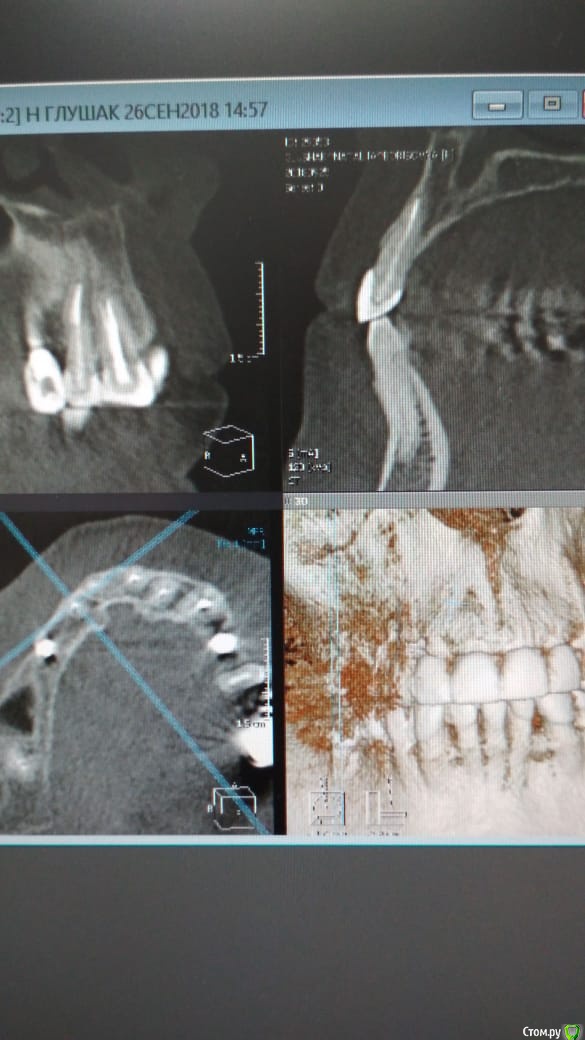

Alexandr_doc Опубликовано 26 сентября, 2018 Автор Поделиться Опубликовано 26 сентября, 2018 Прошу извинить за задержку. Прикладываю срезы со свежего КТ. Поступили предложения о хир удлинении, на мой взгляд это в данной ситуации очень рискованно. Ссылка на комментарий

kramer Опубликовано 26 сентября, 2018 Поделиться Опубликовано 26 сентября, 2018 Может, прозвучит банально, но нет смысла резцы вывести из окклюзии? По КТ плотный контакт с антагонистами Ссылка на комментарий

Alexandr_doc Опубликовано 21 сентября, 2018 Автор Поделиться Опубликовано 21 сентября, 2018 Точно ли на кт нет изменений на корнях зубов? Мне на рентгеновских снимках что-то видится. жесткая каппа на верхний зубной ряд - я бы начал с этого.Нижние резцы устойчивы?Чем вам не нравится глубокая поддесневая препаровка? Десна выглядит также как и на интактных зубах НЧ.Как проверяется работа на предмет локальной перегрузки - не знаю, расскажите пожалуйста.На кт изменений нет, мне хотелось их найти, но нет. Мне будет не сложно сделать срезы и приложить их к посту, рассматривал некачественное эндо как один из первых причинных факторов. Жесткая капа какая? Какой дизайн и схему порекомендуете? Десна действительно сейчас выглядит также как и в других участках. При гипсовке в ЦС проверены: наличие первого контакта на фронтальной группе, проверена схема направляющих, распределение контактов на моделях. Ссылка на комментарий